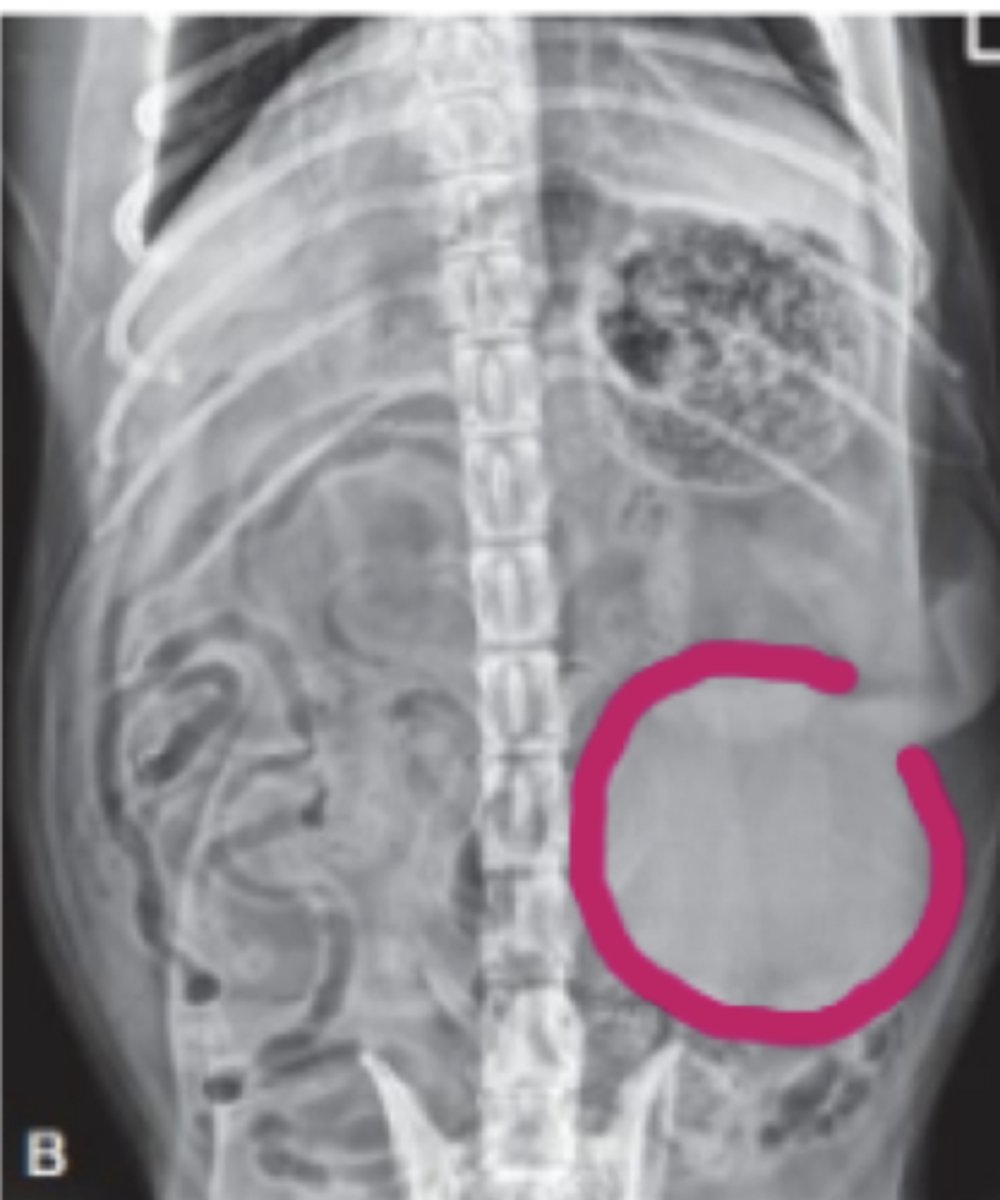

megacolon

patología: